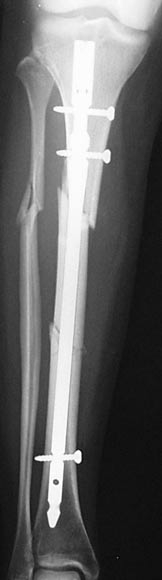

Example X-ray Images

Repair of Tibial Shaft Fracture with Intramedullary Nail